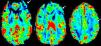

La afasia es una alteración adquirida del lenguaje debida a una lesión cerebral, que se caracteriza por errores en la producción, la denominación o la comprensión del lenguaje. Aunque la mayoría de las afasias suelen ser mixtas, desde un punto de vista práctico se clasifican en diferentes tipos según sus rasgos clínicos principales: afasia de Broca, afasia de Wernicke, afasia de conducción, afasia transcortical y alexia con o sin agrafia. Presentamos los hallazgos clínicos de los principales subtipos representándolos con casos radiológicos, y proporcionamos una revisión actualizada de la red del lenguaje con imágenes de resonancia funcional y de tractografía.

Aphasia is an acquired language disorder due to a cerebral lesion; it is characterized by errors in production, denomination, or comprehension of language. Although most aphasias are mixed, from a practical point of view they are classified into different types according to their main clinical features: Broca's aphasia, Wernicke's aphasia, conduction aphasia, transcortical aphasia, and alexia with or without agraphia. We present the clinical findings for the main subtypes of aphasia, illustrating them with imaging cases, and we provide an up-to-date review of the language network with images from functional magnetic resonance imaging and tractography.